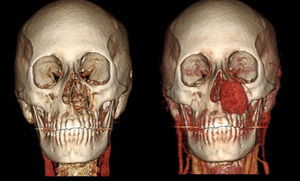

Mujer de 37 años con tiempo de enfermedad de 9 meses, caracterizado por la presencia de una tumoración en la región nasogeniana izquierda de crecimiento rápido. La tomografía con contraste de macizo facial muestra una lesión sólida, homogénea, de márgenes parcialmente definidos, dependiente del maxilar superior izquierdo (figs. 1 y 2).